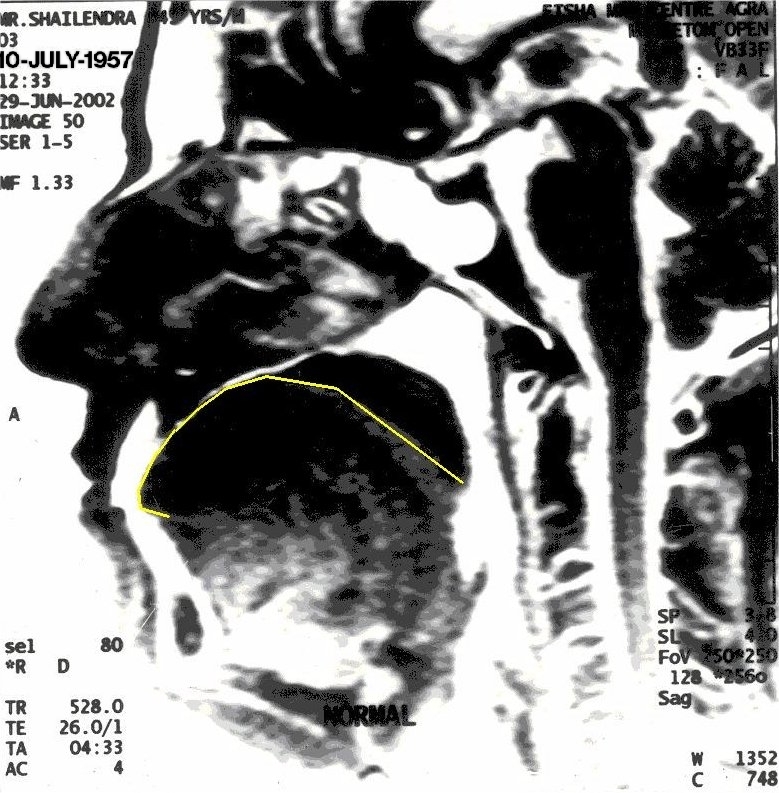

Before Khechari Mudra

The position of tongue is outlined in yellow

With Khechari Mudra